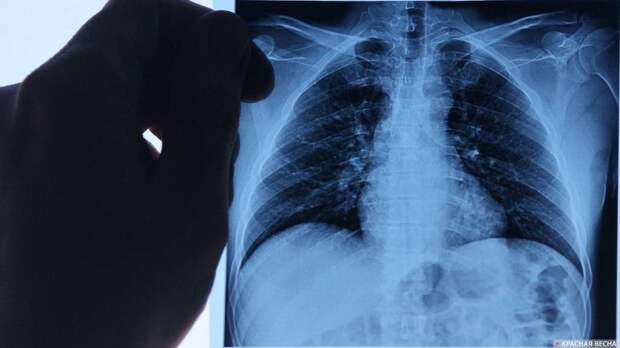

Впервые инновационный тест для диагностики туберкулеза, созданный в России, включен в рекомендации ВОЗ (Всемирная организация здоровья), которые являются основным документом для медиков всех стран, 3 октября сообщила главный внештатный фтизиатр Минздрава России Ирина Васильева. «Впервые российский инновационный тест для диагностики туберкулеза и выявления пациентов с высоким риском развития активного туберкулезного процесса вошел в консолидированные методические рекомендации ВОЗ, которые являются основным предписанием для мирового врачебного сообщества», — отметила Васильева.

Диаскин-тест, инновационная разработка ученых их России, является новым классом кожных тестов и очень точно установливает факт заражения организма микобактериями туберкулеза. Использование этого теста помогает избежать ложноположительных результатов. Это позволяет проводить профилактику и лечить туберкулез на ранней стадии, подчеркнула фтизиатр. ВОЗ считает диаскин-тест наиболее эффективным методом выявления туберкулеза, алтернативным туберкулиновой пробе (реакции Манту) и анализу высвобождения гамма-интерферона IGRA. Напомним, диаскин-тест был создан в лаборатории биотехнологии НИИ молекулярной медицины ММА им. И. М. Сеченова. В России диаскин-тест используется для диагностики взрослых с 2009 года, а с 2017 года — для выявления заболевания туберкулезом у детей с семи лет. Отметим также, в 2021 году Россию исключили из списка стран, по версии ВОЗ, с высоким риском туберкулеза. Россия была в этом списке 22 года.